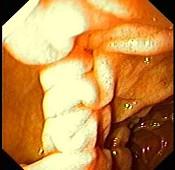

问题 女性,45岁。腹部饱胀不适2年余。表情自然,皮肤无黄染,未见蜘蛛痣,巩膜无黄染。腹平坦,腹肌软,全腹无压痛反跳痛,肝脾肋缘下0.5cm,胃镜检查如下图,诊断为 ( )

选项 A、十二指肠穿孔 B、十二指肠雍滞症 C、十二指肠溃疡 D、十二指肠炎 E、十二指肠憩室

答案 E